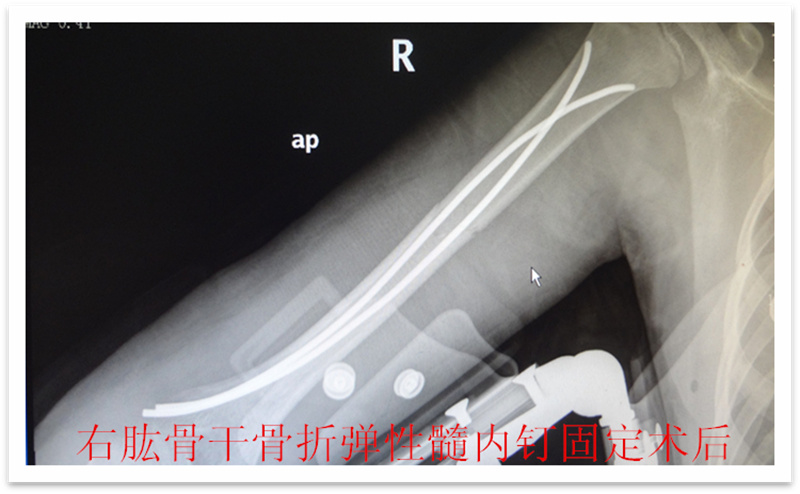

,弹性髓内钉内固定解决了这个矛盾。有人说,弹性髓内钉的出现是上天对儿童的恩惠。的确,弹性髓内钉是治疗小儿长管状骨骨骨折的一种理想、可靠的内固定方法。弹性髓内钉技术发源于法国,在欧洲广泛应用后,现已为全球所接受,被称为是儿童骨科界的一次革命。徐州儿童医院骨一科应用弹性髓内钉技术治疗四肢长管状骨骨折,具有创伤小、恢复快、并发症相对少,孩子能较快恢复正常生活、学习等优点。该技术先将骨折闭合复位,通过微小的切口将特制的弹性髓内钉置入骨髓腔,达到固定骨折的目的。适用于肱骨,股骨,尺桡骨等部位的常见骨折。